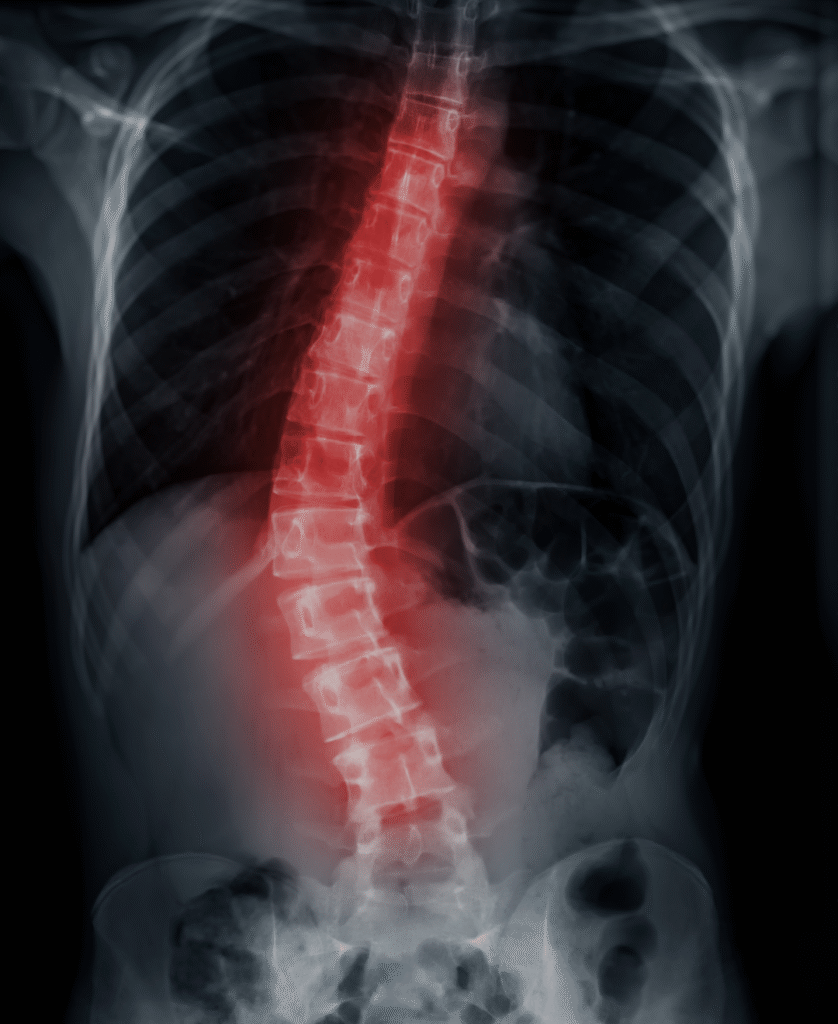

Aprenda a avaliar, tratar e se posicionar com segurança no atendimento a crianças e adolescentes com escoliose – com lógica clínica, evidência científica e exercícios corretivos individualizados.

A maioria dos fisioterapeutas evita atender escoliose por medo de errar ou por acreditar que é papel exclusivo do ortopedista. Mas quem domina a avaliação e o tratamento correto se torna referência, conquista a confiança de pais e médicos — e se destaca com um serviço que poucos oferecem.